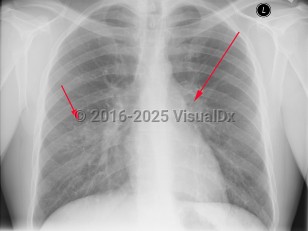

Tuberculosis in Child

The tubercular bacilli from the infective droplet are taken up by the alveolar macrophages, particularly in the upper and mid-lung zones, which have the highest air flow rates. The breach of the bacteria into the subpleural interstitium causes a local inflammation and consolidation with an exudate and cellular infiltrate. This hallmark of primary pulmonary infection is called the Ghon focus. The bacilli are then rapidly taken up by the mediastinal lymph nodes (hilar and/or paratracheal), resulting in their enlargement and liquefaction, which liberates bacilli that can spread hematogenously throughout the body, seeding different organs. The Ghon focus and the mediastinal lymph node enlargement form the primary or Ranke complex. In most patients, the infection remains latent, being forever contained by the development of cell-mediated immunity that results within 3 weeks to 3 months in a positive skin (tuberculin) test. However, in 5%-10% of patients, mostly within 2-3 years, this initial infection evolves toward active TB. This progression is more common in immunosuppressed states such as AIDS and in children younger than 5 years. While pulmonary TB is the most common form of TB in adults and children, extrapulmonary TB can occur in any age group, although it is more common in younger age groups (eg, tuberculous lymphadenitis).

Symptoms of pulmonary TB are nonspecific and include anorexia, fatigue, anemia, weight loss, fevers, and night sweats. Cough is usually productive, and hemoptysis may occur. Pleural involvement may lead to chest pain and dyspnea. Physical examination findings include rales and signs of consolidation. Auscultation over cavities may reveal amphoric breath sounds (like the sound made by blowing across the mouth of a jar). Signs of pleural effusion may also be found. Pericarditis and pericardial effusion can occur.